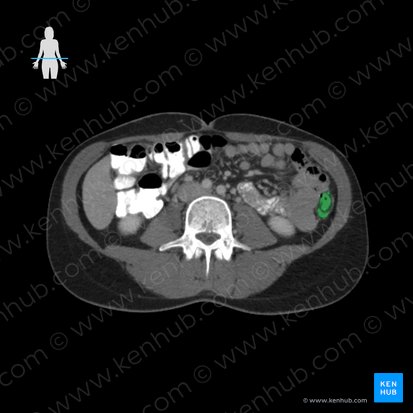

Descending colon

The descending colon is a segment of the large intestine positioned within the left paracolic gutter of the posterolateral abdominal wall. It extends from the left hypochondriac region and runs through the left flank to reach the left iliac fossa. Beginning at the left colic flexure proximally, it descends vertically and becomes continuous with the sigmoid colon distally.

In adults, the descending colon measures about 25–30 cm. It is a retroperitoneal organ, with its anterolateral surface covered by parietal peritoneum that attaches it to the posterior abdominal wall. It runs anterior to the lateral border of the left kidney and in about a third of people, the distal portion of the descending colon has a short mesentery.